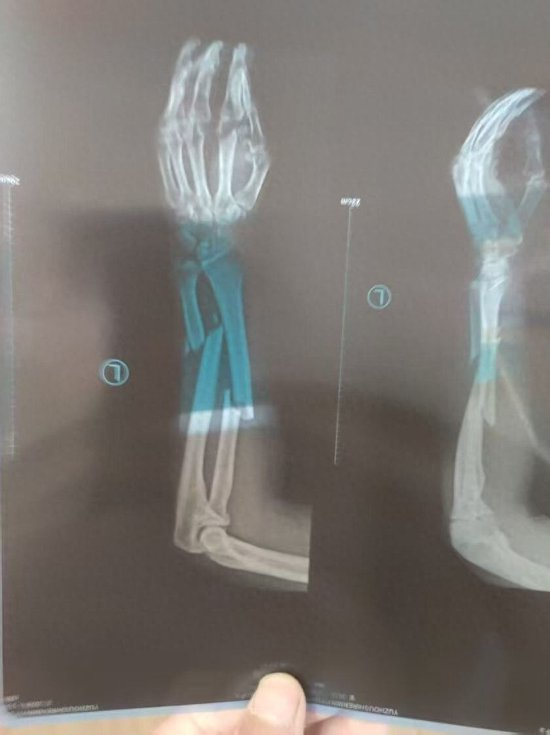

王先生家住河南禹州市,是禹州市神后镇白峪村的河南平禹新明煤业有限公司工人。2022年5月9日4时30分左右,王先生在矿井下风巷打锚索,手扶锚索托盘过程中,左胳膊被钻机拧伤,当地医院诊断为左尺桡骨粉碎性骨折、左尺骨茎突骨折。